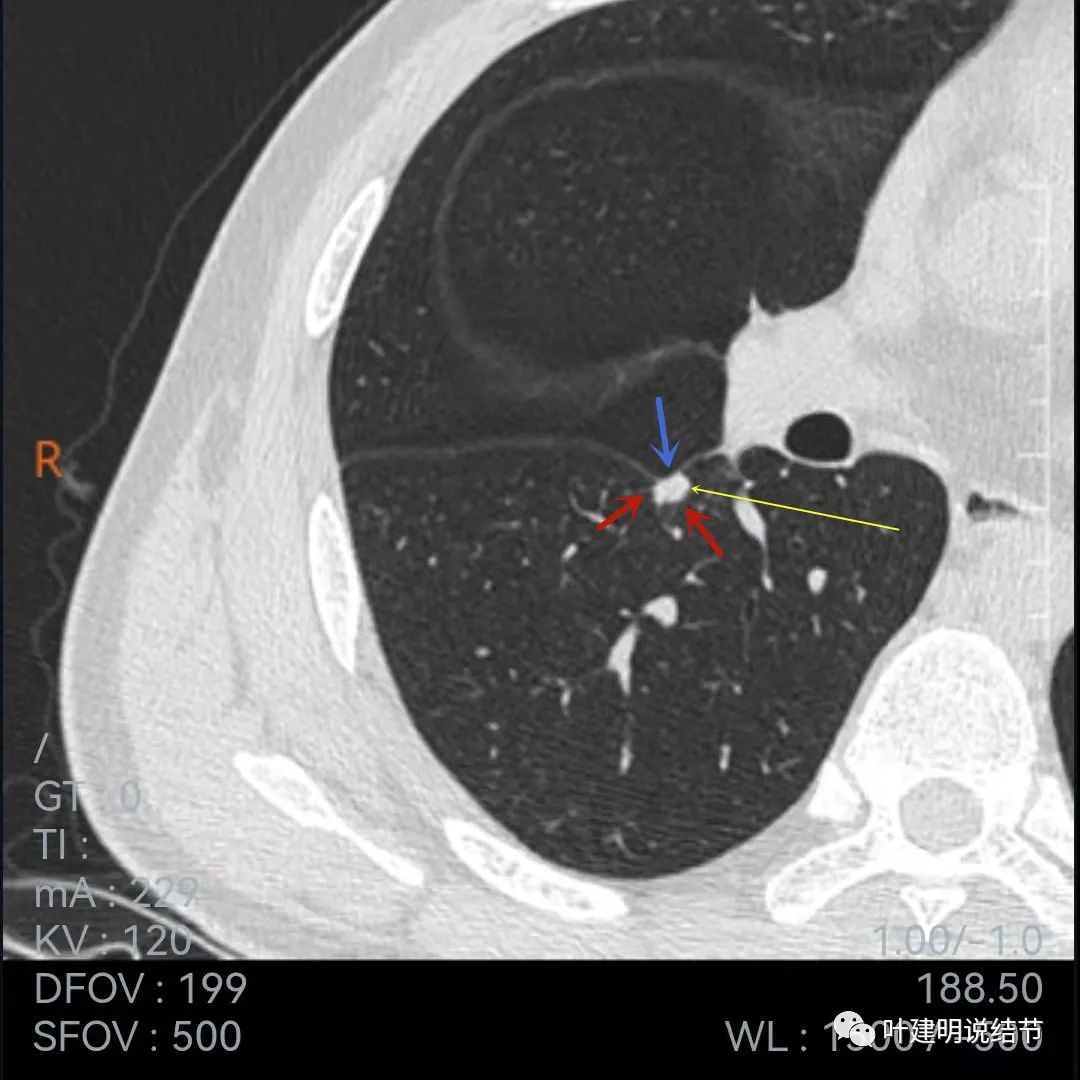

再来看当地医院的靶扫描:

病灶叶间胸膜凹陷,有细毛刺(紫色箭头),但毛刺与病灶大小相比感觉长了点

中间密度还是略低(黄色箭头),胸膜牵拉仍明显(蓝色箭头)

细毛刺(紫色)、胸膜凹陷(蓝色)以及中间偏低密度(黄色)

上图棘突样征象较明显(紫色箭头)